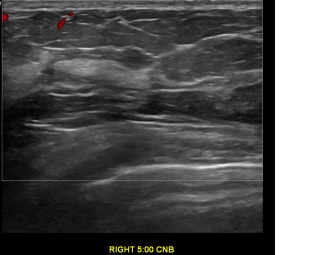

상기환자는 양성추정혹 추적관찰 하시는  30대중반

여성분으로 의심스러운 우측혹 조직검사 시행해 상피내암으로 진단되었습니다